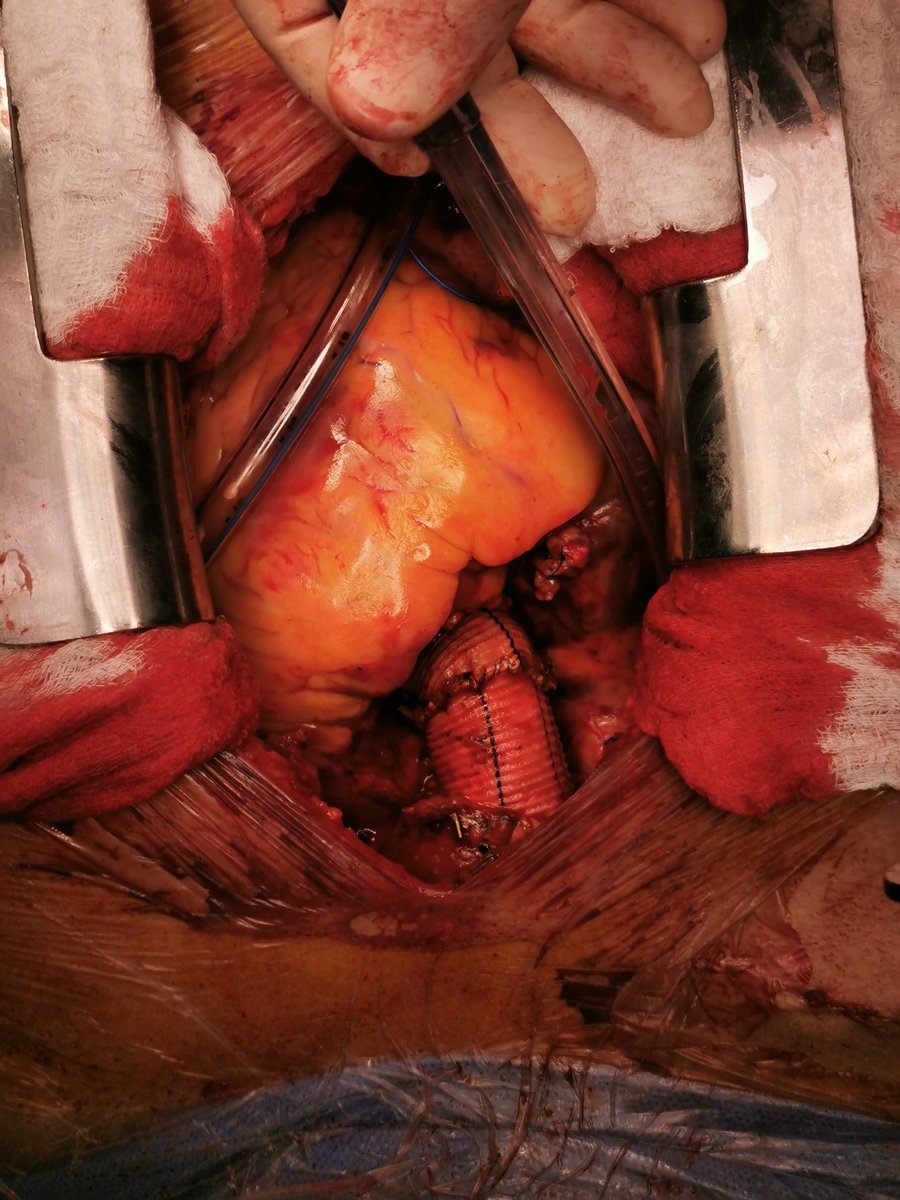

حالة تسلخ للشريان الاورطي/ الابهري قبل وبعد التدخل الجراحي.

الصور من الزميل الفاضل د. حمد الحبيب @hamad_alhabib